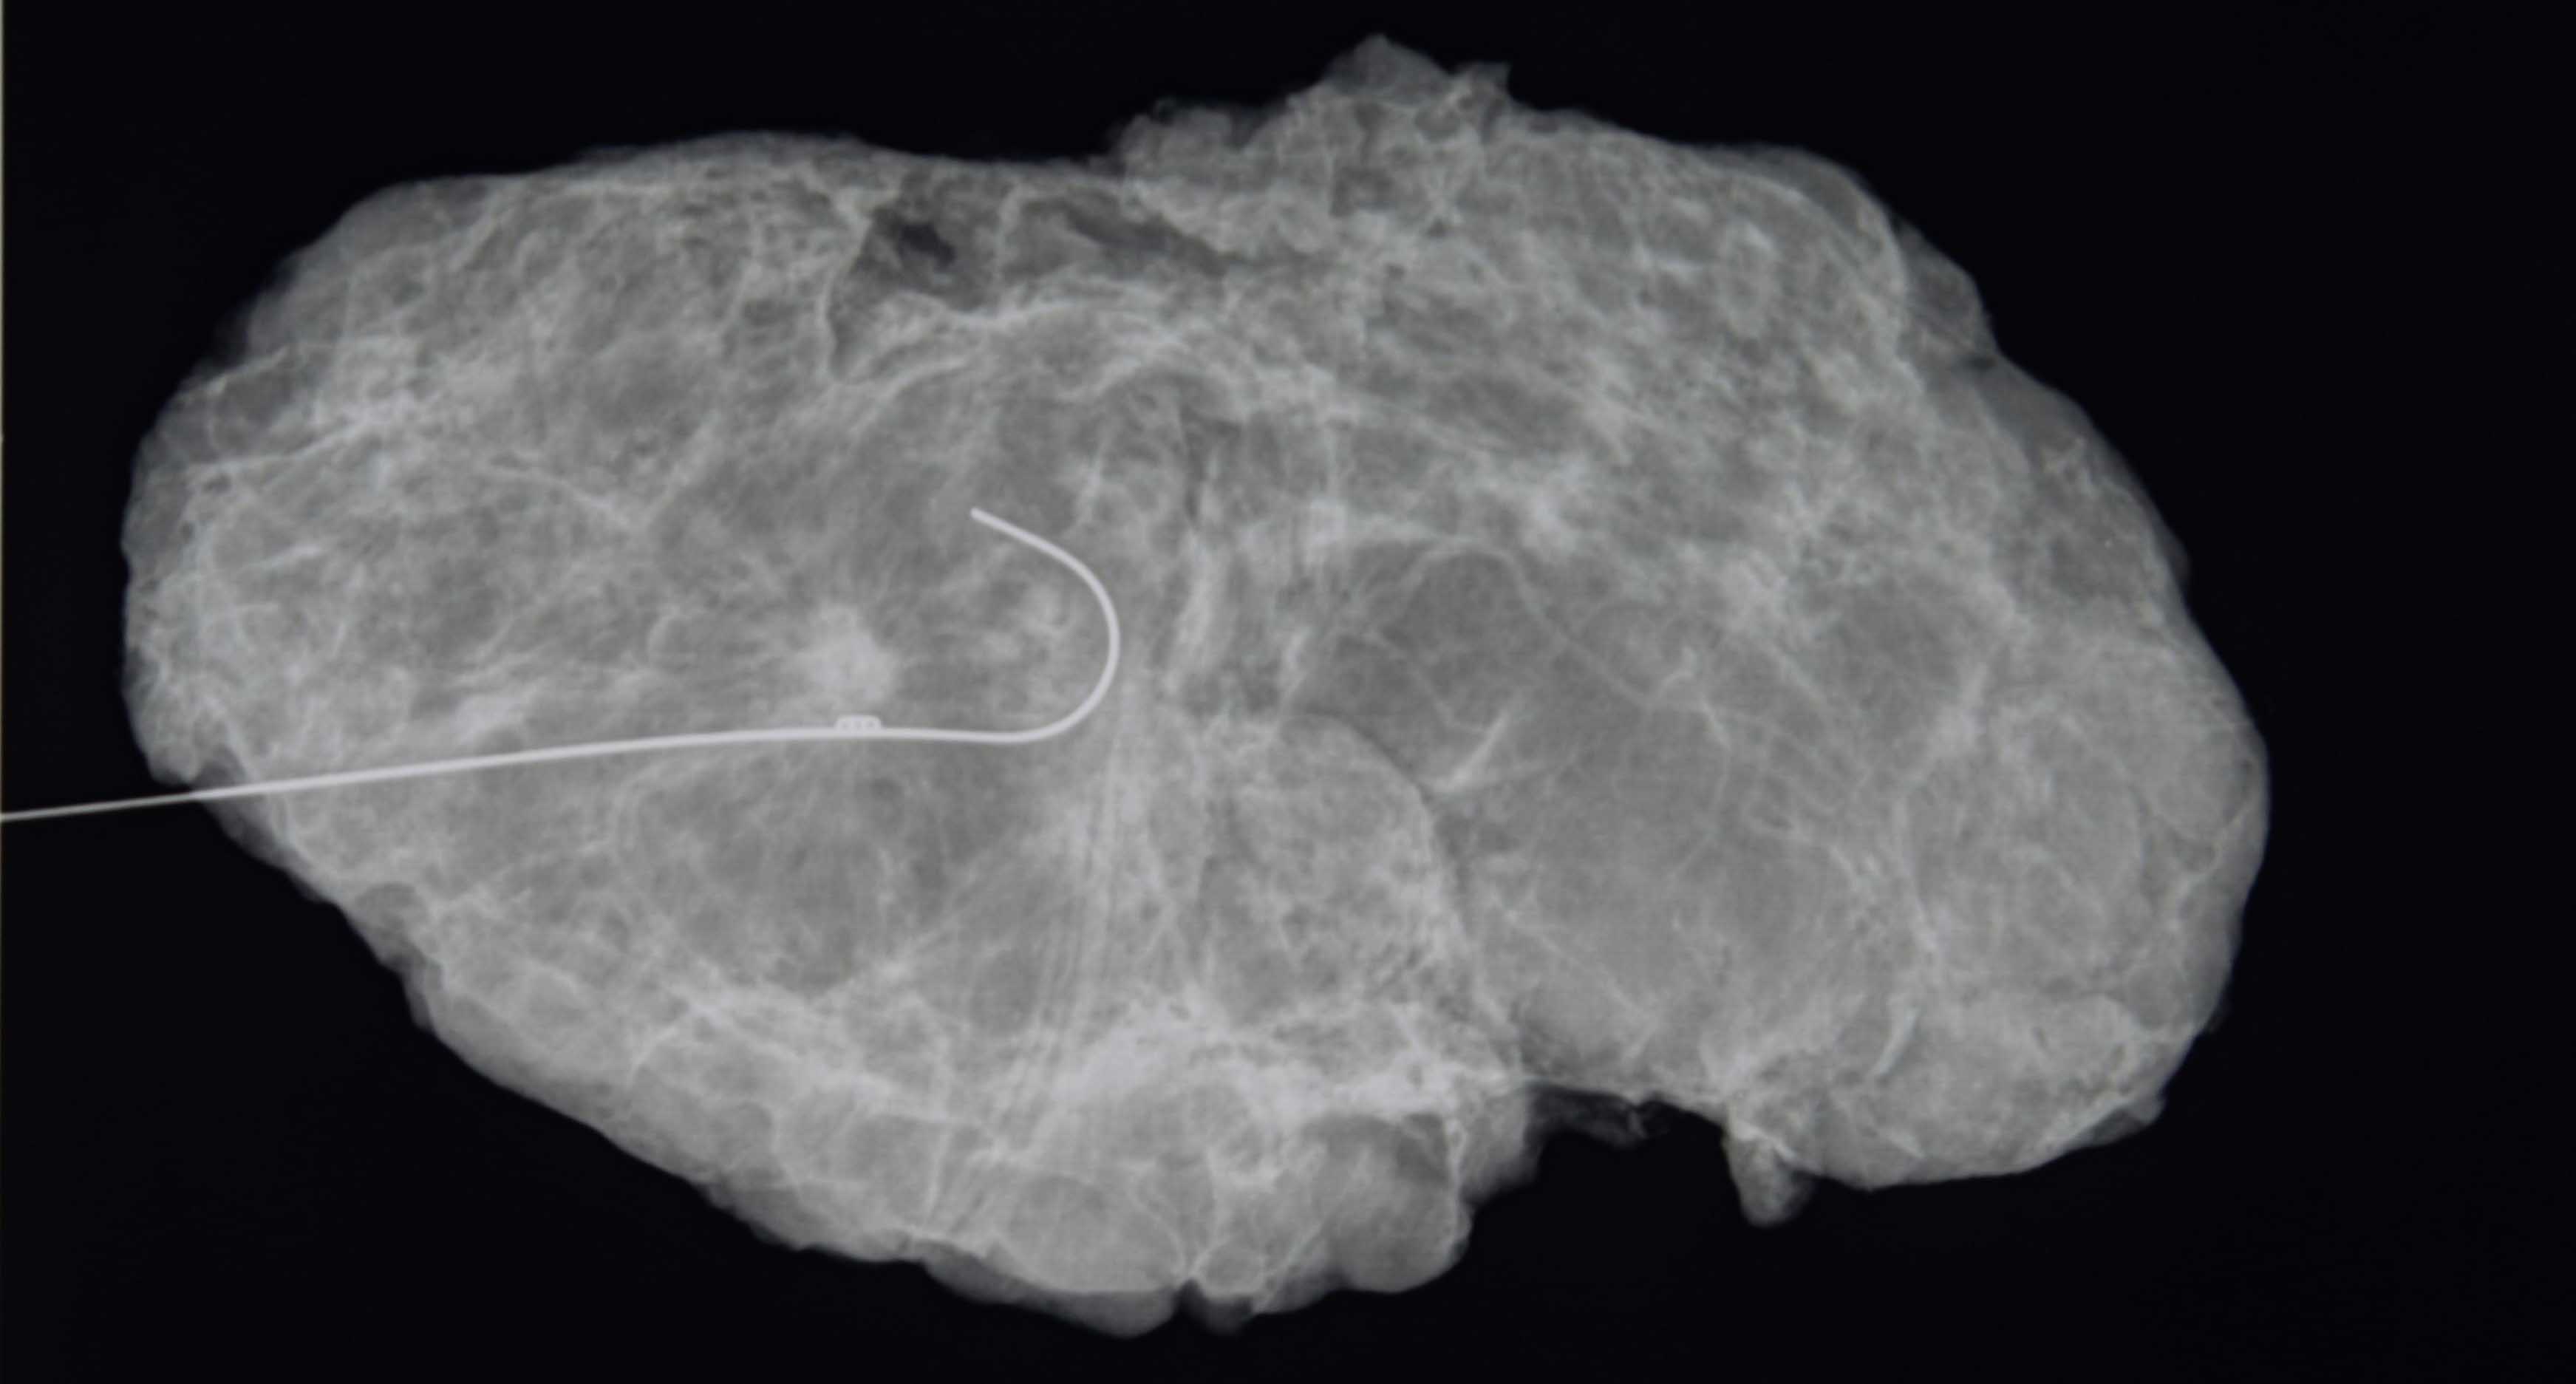

Los investigadores querían saber: ¿Este dogma seguía siendo cierto? Siguieron a casi 200 mujeres con dos o tres tumores en un seno que se sometieron a lumpectomías seguidas de radiación. Las pacientes tenían entre 40 y 87 años de edad.

Para participar en el estudio, sus tumores tenían que tener menos de 5 centímetros y estar separados por 2 a 3 centímetros de tejido mamario normal. Después de cinco años, solo el 3% vio que el cáncer regresaba, tasas similares a las de estudios previos de lumpectomía en pacientes con un solo tumor.

Eso habría arrojado mejores datos, pero sería casi imposible encontrar mujeres dispuestas a ser asignadas al azar, dijo Boughey, lo que hace que ese experimento no sea práctico. En el estudio, las mujeres que se sometieron a una resonancia magnética antes de la cirugía obtuvieron los mejores resultados, lo que sugiere que las exploraciones por resonancia magnética pueden ayudar a los cirujanos a ser más minuciosos en la extirpación del cáncer.